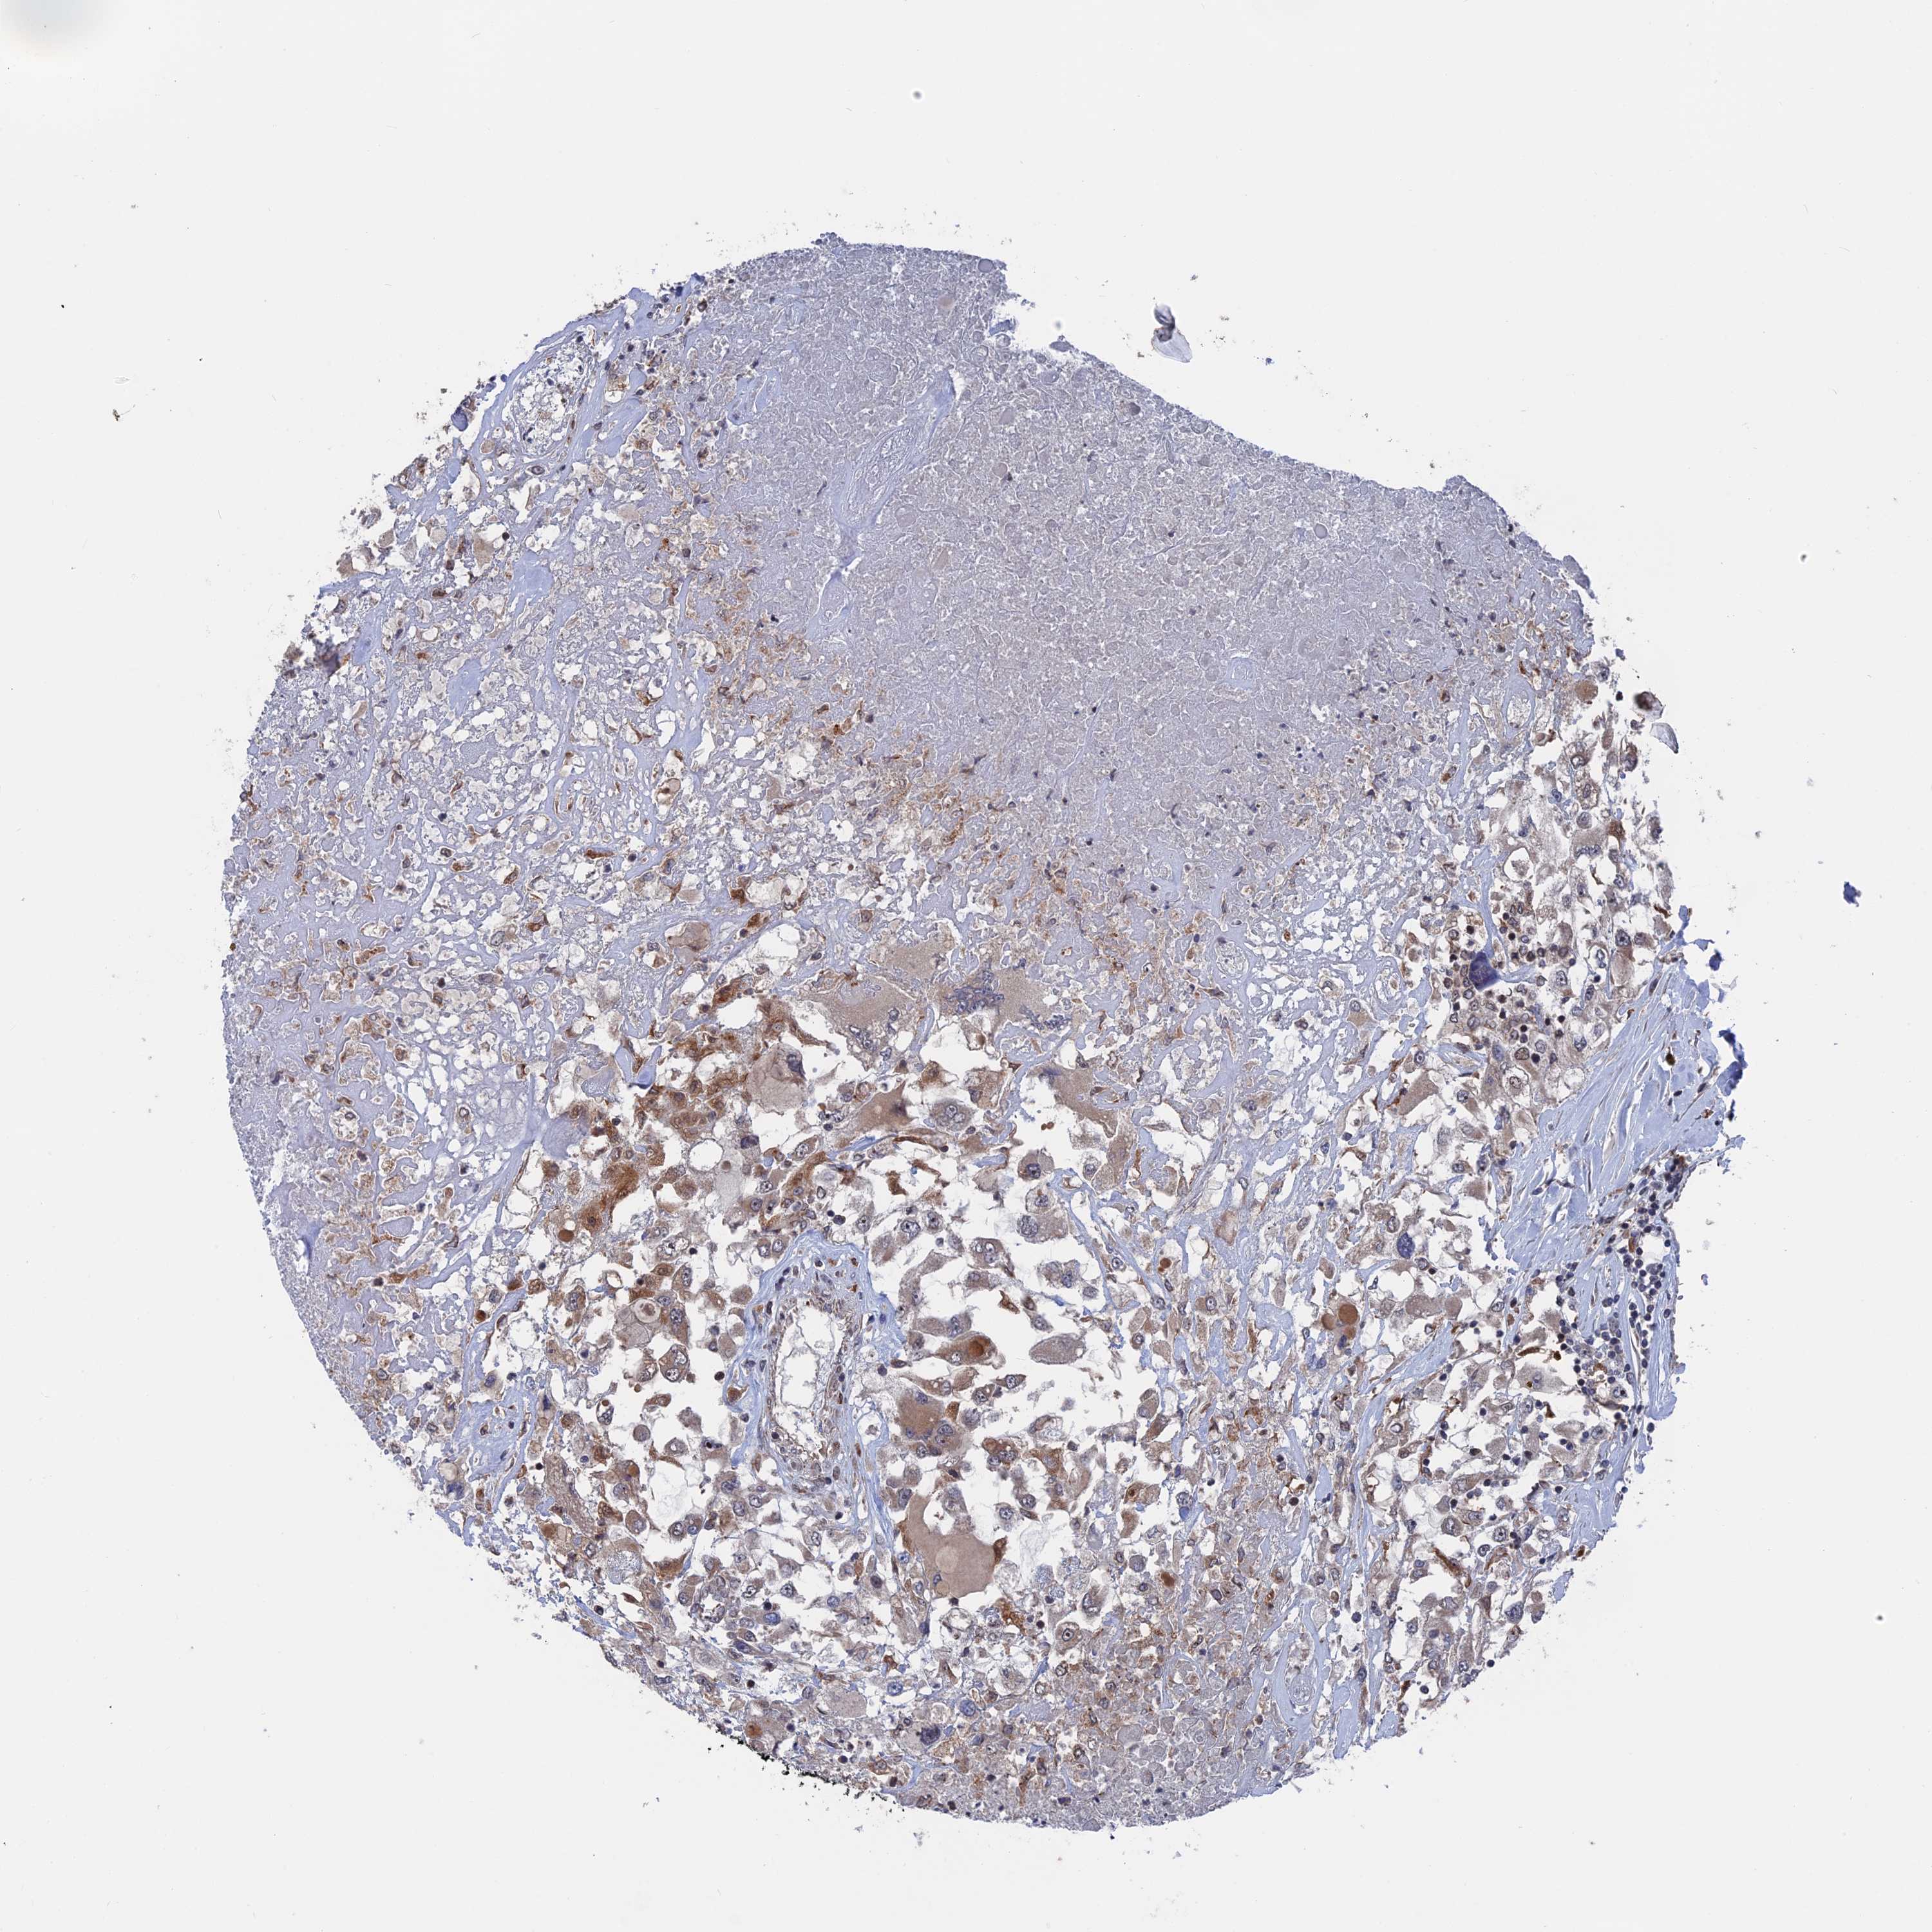

PLA2G15 is potential prognostic, high expression is unfavorable in Kidney Renal Clear Cell Carcinoma (validation)

: 34.29

Average pTPM 27.0

Number of samples 100